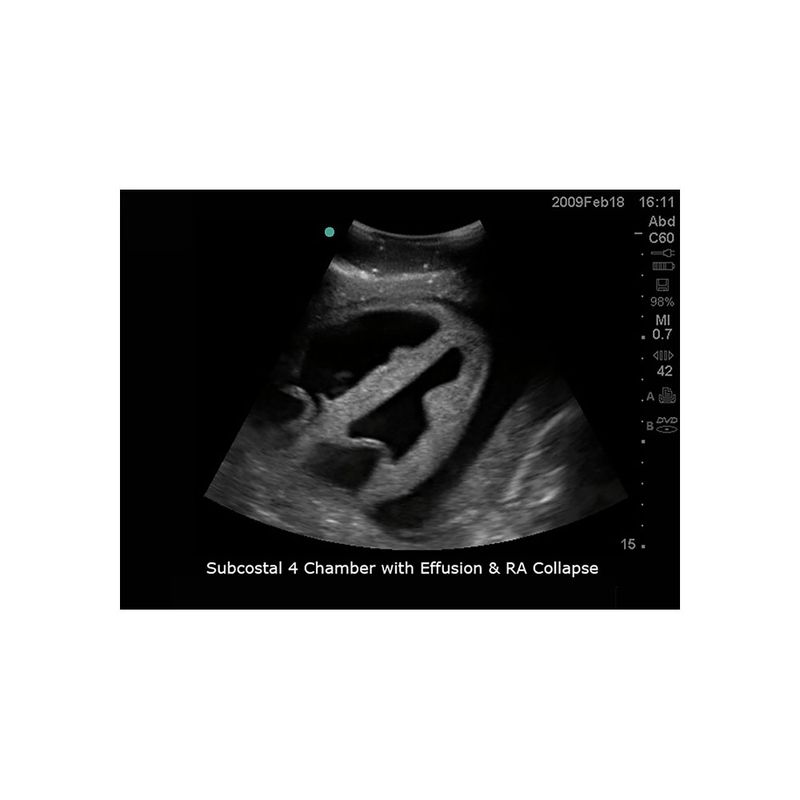

超声引导下心包穿刺术模型

型号:PC-BP003

模型能够与任何带心脏探头的超声影像检查设备连接使用,为练习经胸廓超声引导下心包穿刺训练而设计。